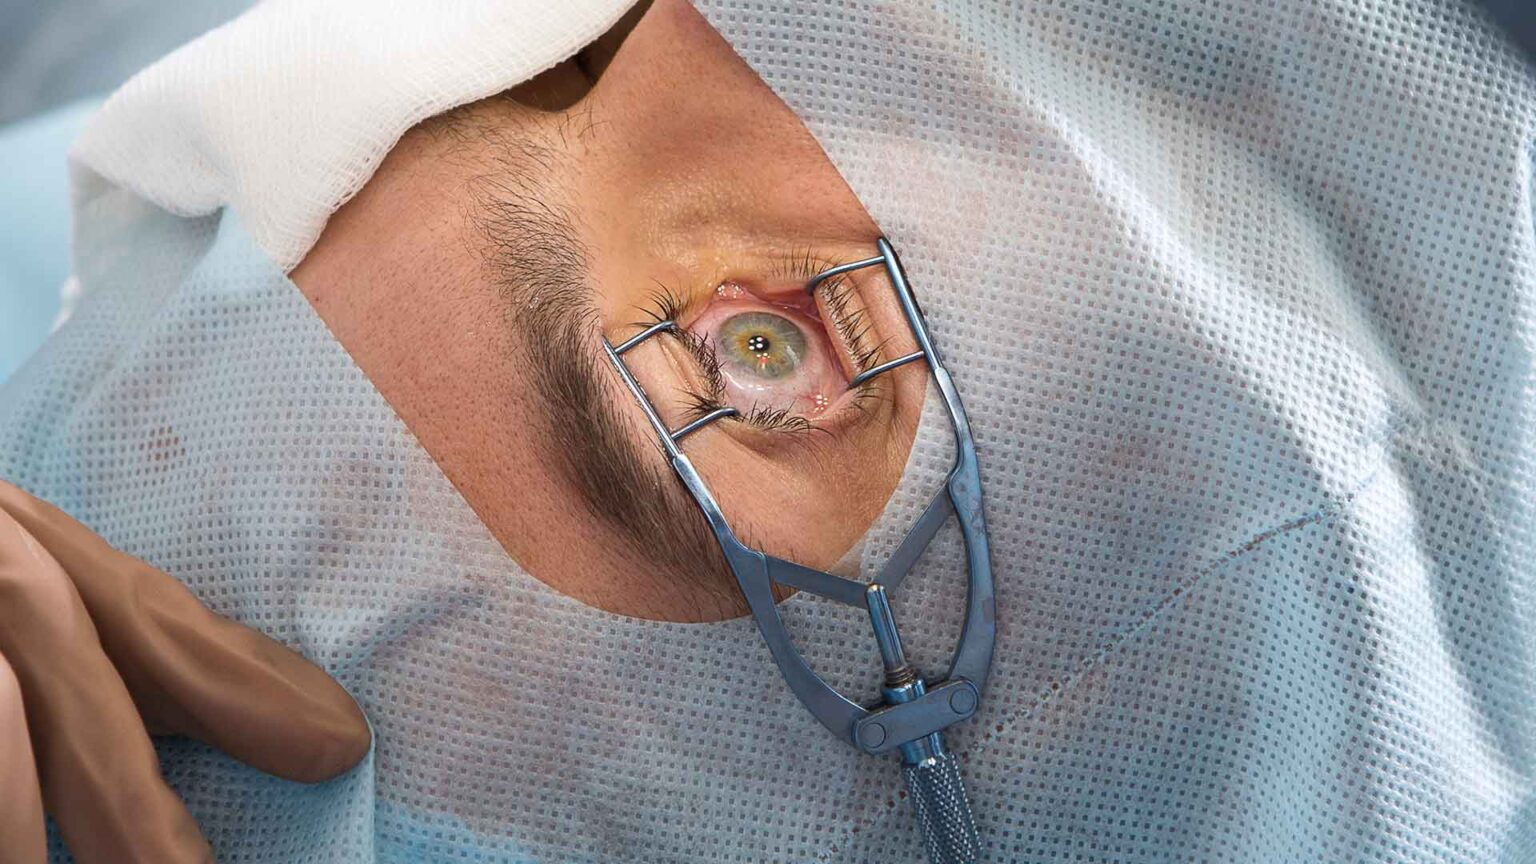

Modernste Ausstattung und Technologie

In unseren hellen und freundlichen Behandlungsräumen arbeiten wir mit hochmoderner Medizintechnik. Dazu gehören state-of-the-art-Operationssäle, modernste bildgebende Verfahren und innovative Operationstechniken. So können wir Ihnen eine optimale Versorgung auf höchstem medizinischen Niveau bieten.

Bildergalerie